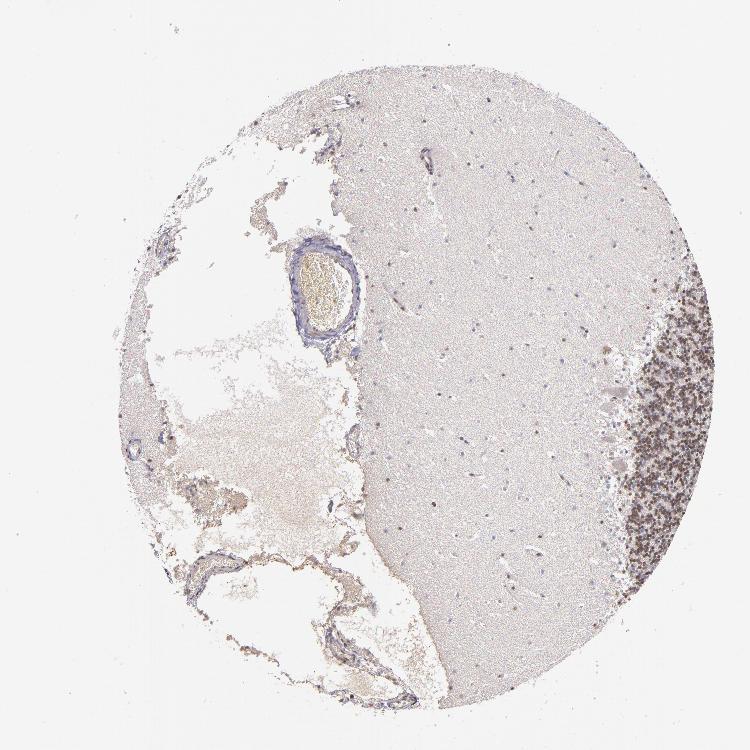

CEREBELLUM - Antibody stainingi

Antibody staining in the annotated cell types in the current human tissue is reported as not detected, low, medium, or high, based on conventional immunohistochemistry profiling in selected tissues. This score is based on the combination of the staining intensity and fraction of stained cells.

Each image is clickable and will lead to virtual microscopy that enables deeper exploration of all samples and also displays staining intensity scores, fraction scores and subcellular localization as well as patient and tissue information for each sample.

Antibody HPA003128Antibody HPA004112Antibody CAB000146

Purkinje cells MediumHigh-

Cells in granular layer MediumLow-

Cells in molecular layer MediumMedium-